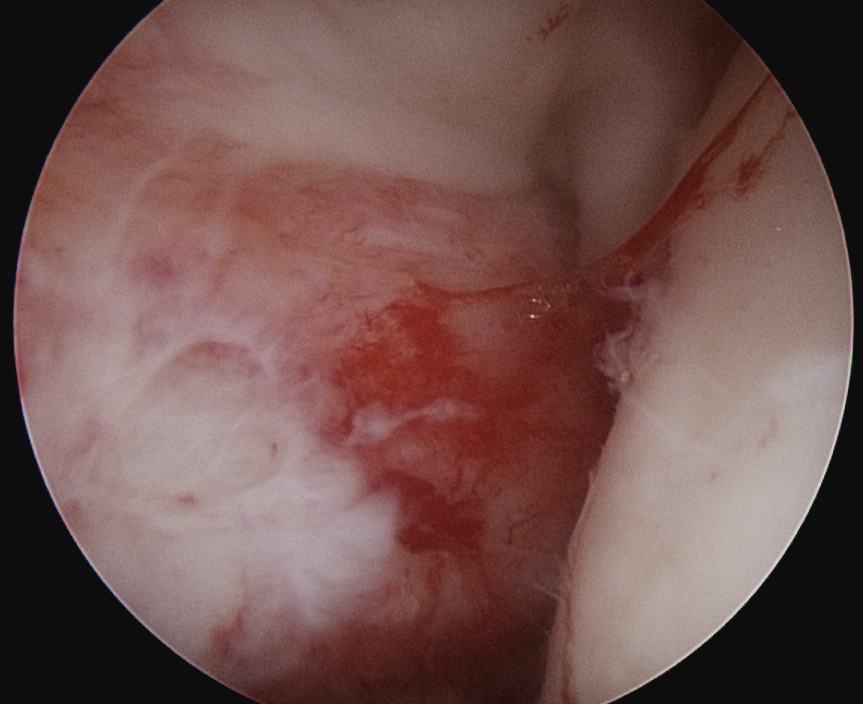

- debride base of Hill Sachs to bleeding bone

- insert anchors at medial aspect of defect

- suture passer / birds beak to take bite of capsule

- tie down into defect